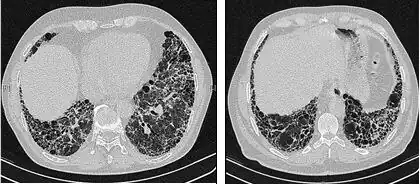

As radiografias de tórax são úteis na rotina de acompanhamento de pacientes com FPI. Infelizmente, as radiografias simples de tórax não são diagnósticas, mas podem revelar volumes pulmonares reduzidos, geralmente com marcas intersticiais reticulares proeminentes próximas às bases pulmonares.[3]

A avaliação radiológica por meio da TCAR é um ponto essencial no caminho do diagnóstico da FPI. A TCAR é realizada usando um scanner tomográfico axial computadorizado convencional sem injeção de agentes de contraste. As fatias de avaliação são muito finas, de 1 a 2 mm.

A TCAR típica do tórax da FPI demonstra alterações fibróticas em ambos os pulmões, com predileção pelas bases e pela periferia. De acordo com as diretrizes conjuntas das ATS, ERS, JRS e ALAT de 2011, a TCAR é um componente essencial da via diagnóstica na FPI, que pode identificar a PIU pela presença de:[3]

- Opacidades reticulares, geralmente associadas a bronquiectasias de tração

- Favos de mel manifestados como espaços aéreos císticos agrupados, geralmente de diâmetros comparáveis (3-10 mm), mas ocasionalmente grandes. Geralmente são subpleurais e caracterizados por paredes bem definidas e dispostos em pelo menos duas linhas. Em geral, uma linha de cistos não é suficiente para definir os favos de mel.

- Opacidades de vidro fosco são comuns, mas menos extensas do que a reticulação.

- Distribuição caracteristicamente basal e periférica, embora muitas vezes irregular.

Tomografia computadorizada de alta resolução do tórax de um paciente com FPI. As principais características são um padrão periférico, predominantemente basal, de reticulação grosseira com favos de mel